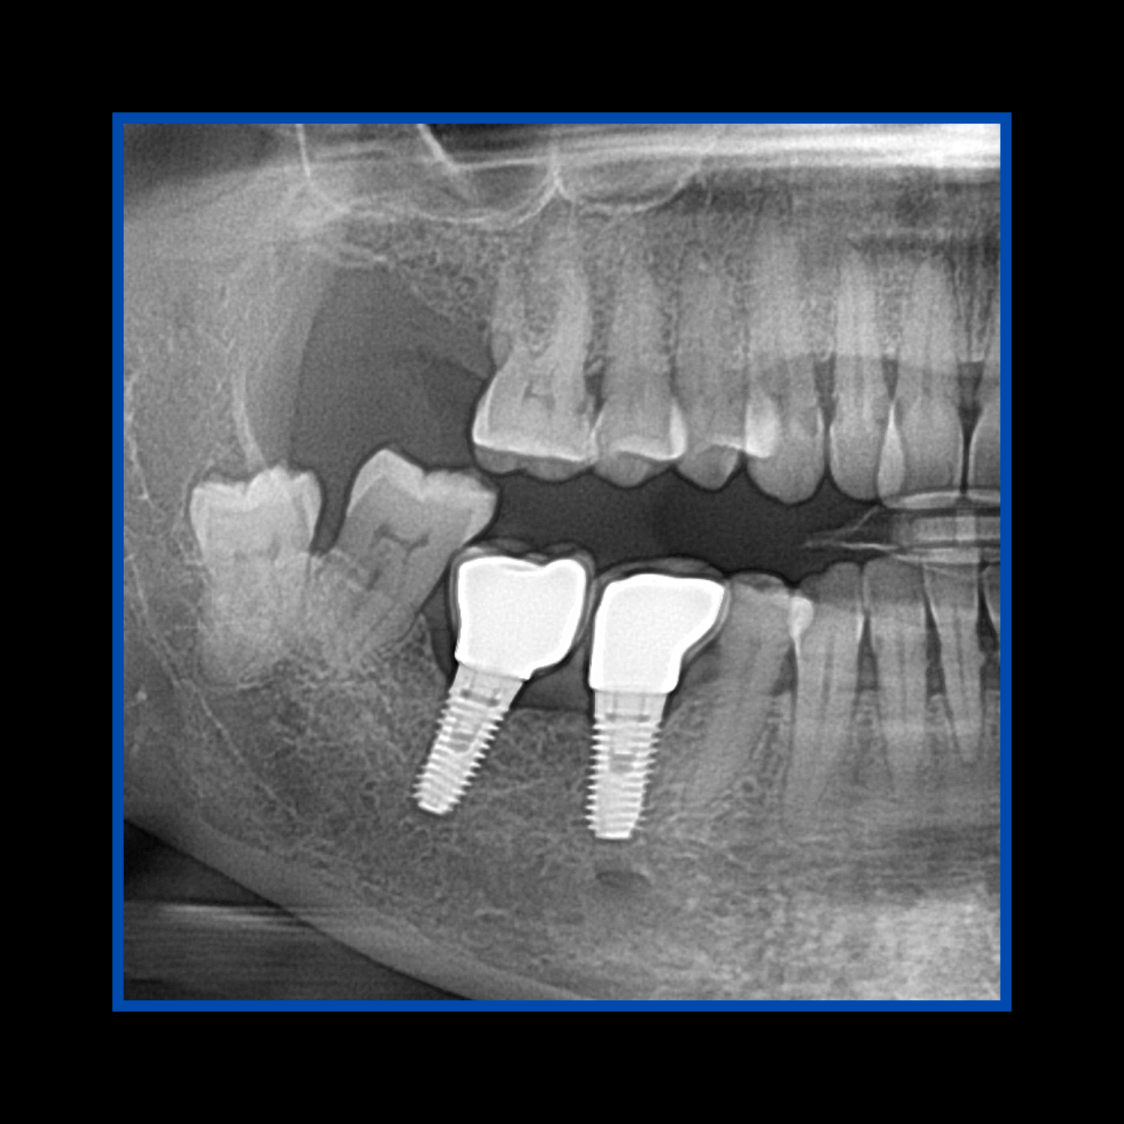

Diş çekiminin yıllar önce yapılmış olmasına bağlı olarak ince kemik varlığında implant ve kemik grefti uygulandı.